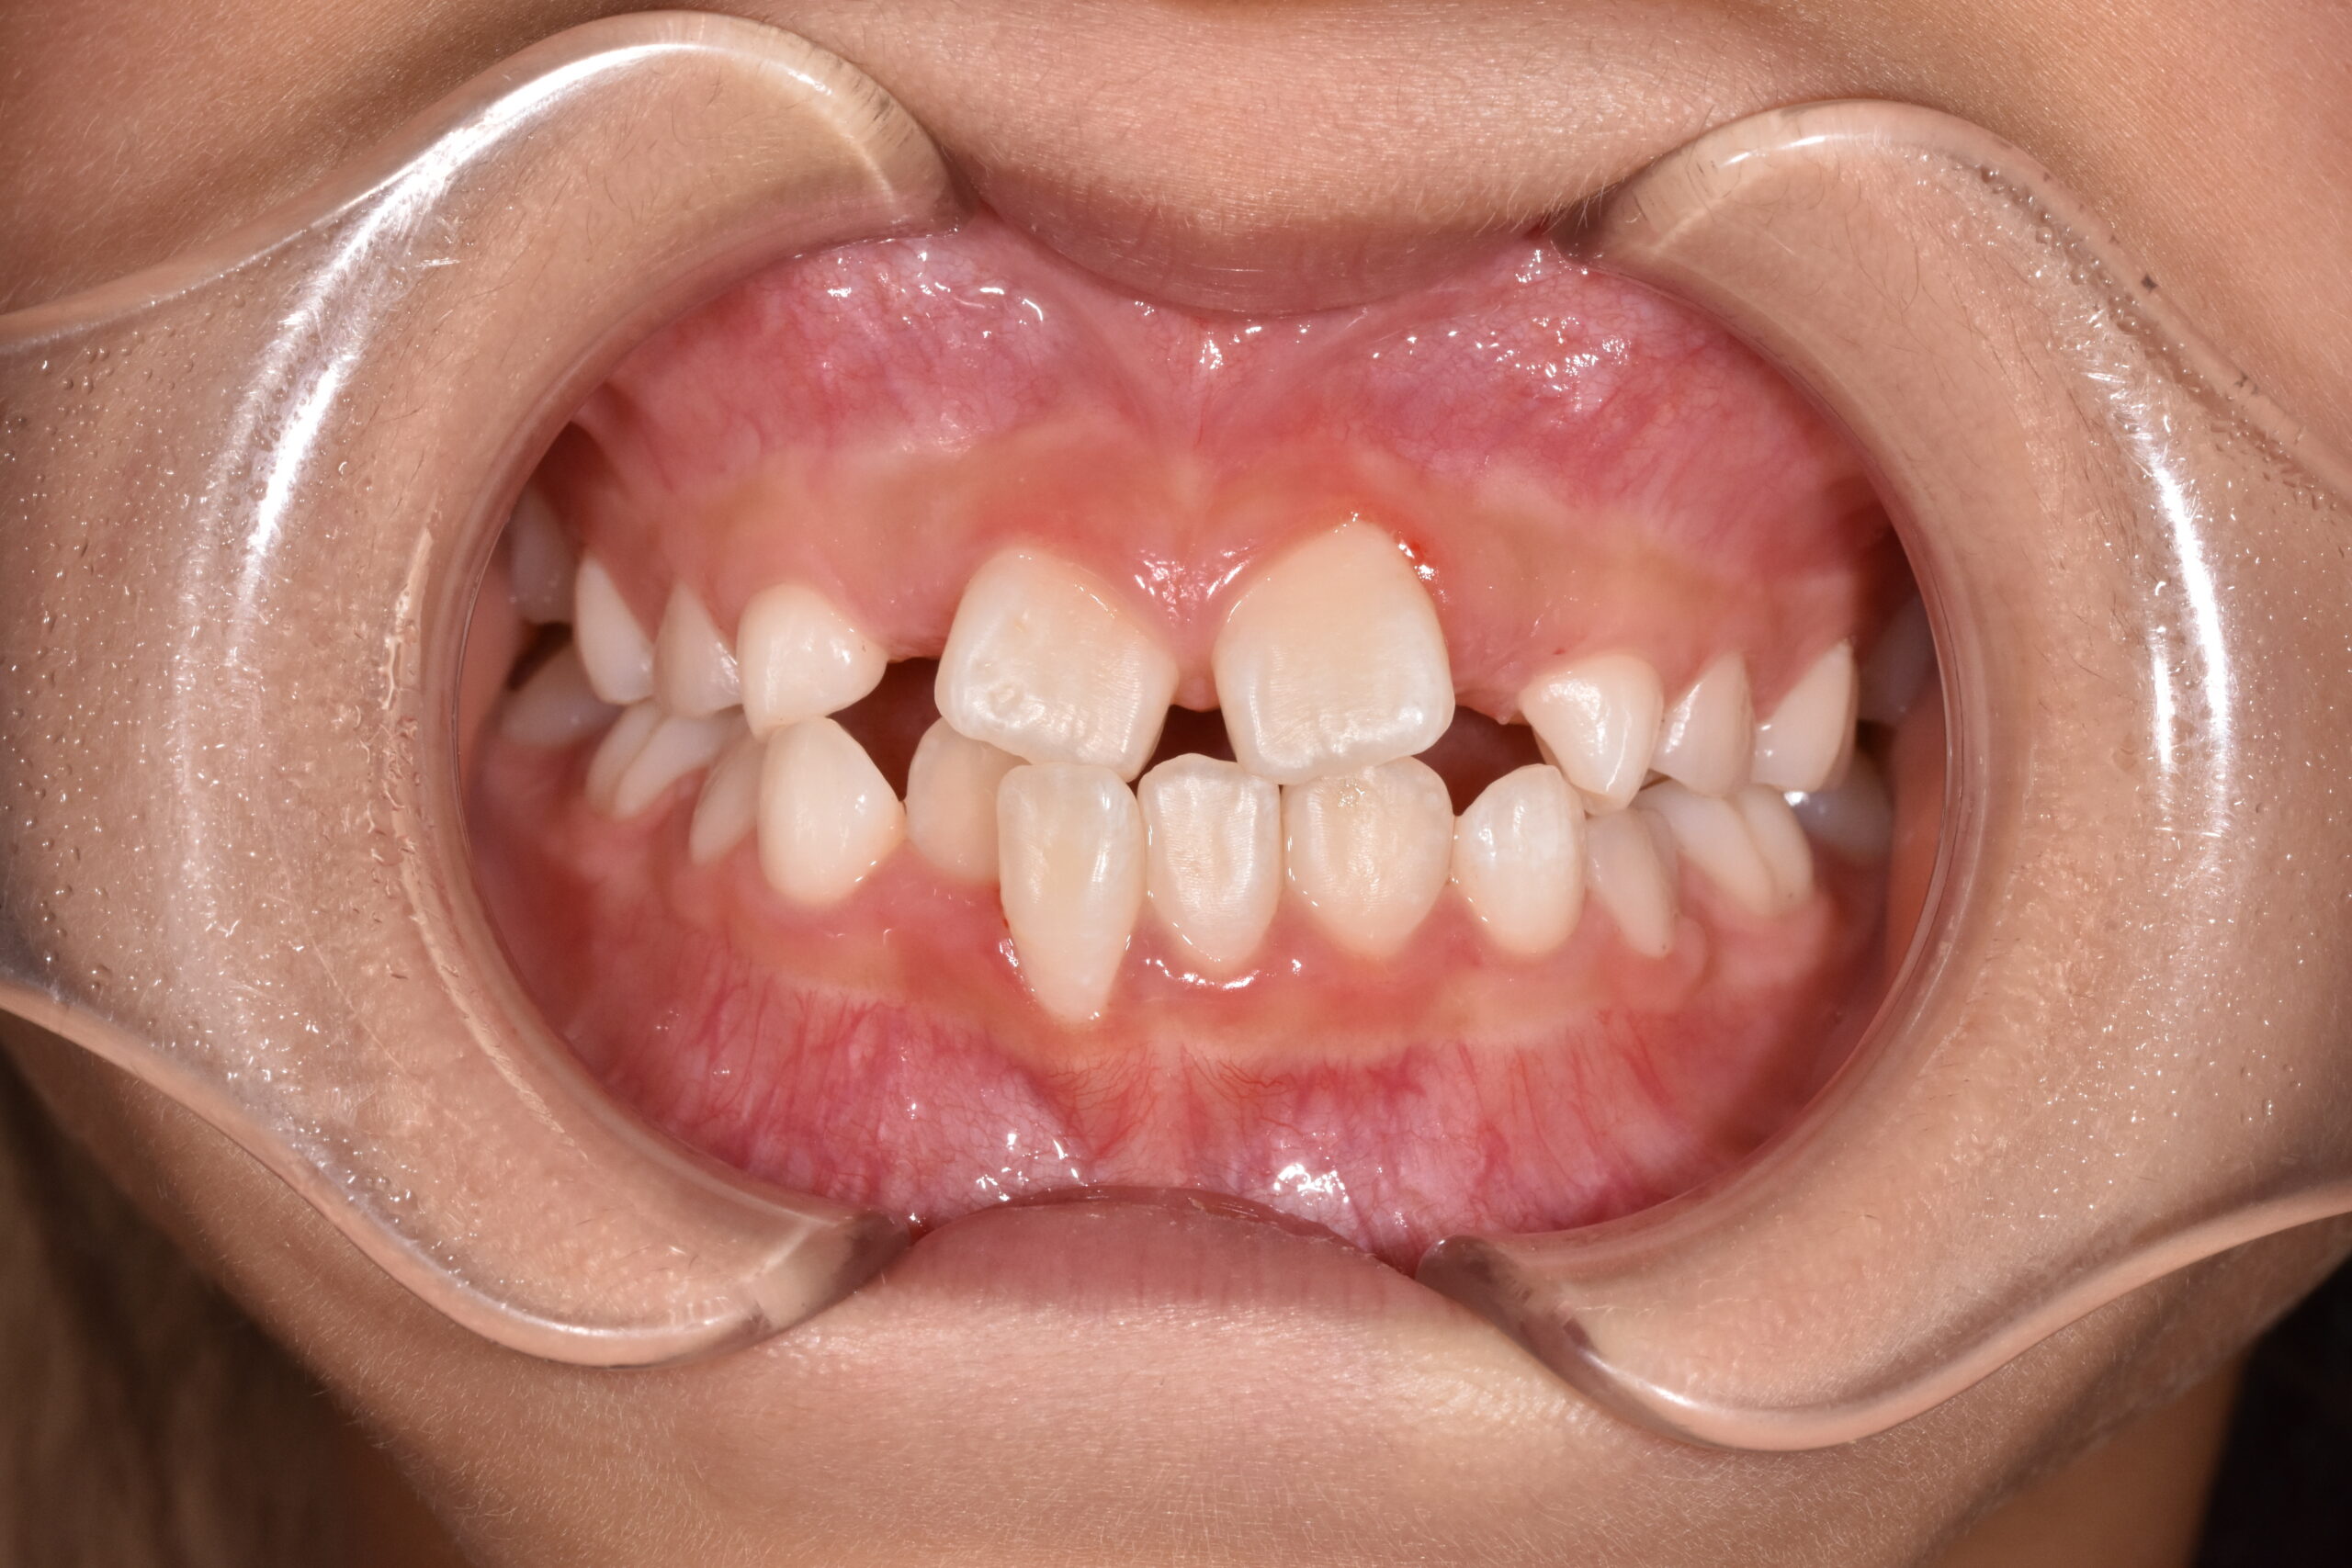

反対咬合・叢生 7歳 女の子

7歳 女性

治療前

年齢:7歳 女の子

お悩み:

前歯が逆に噛んでいる(受け口)

状態:

骨格:受け口傾向

歯並び:前歯のかみ合わせが逆